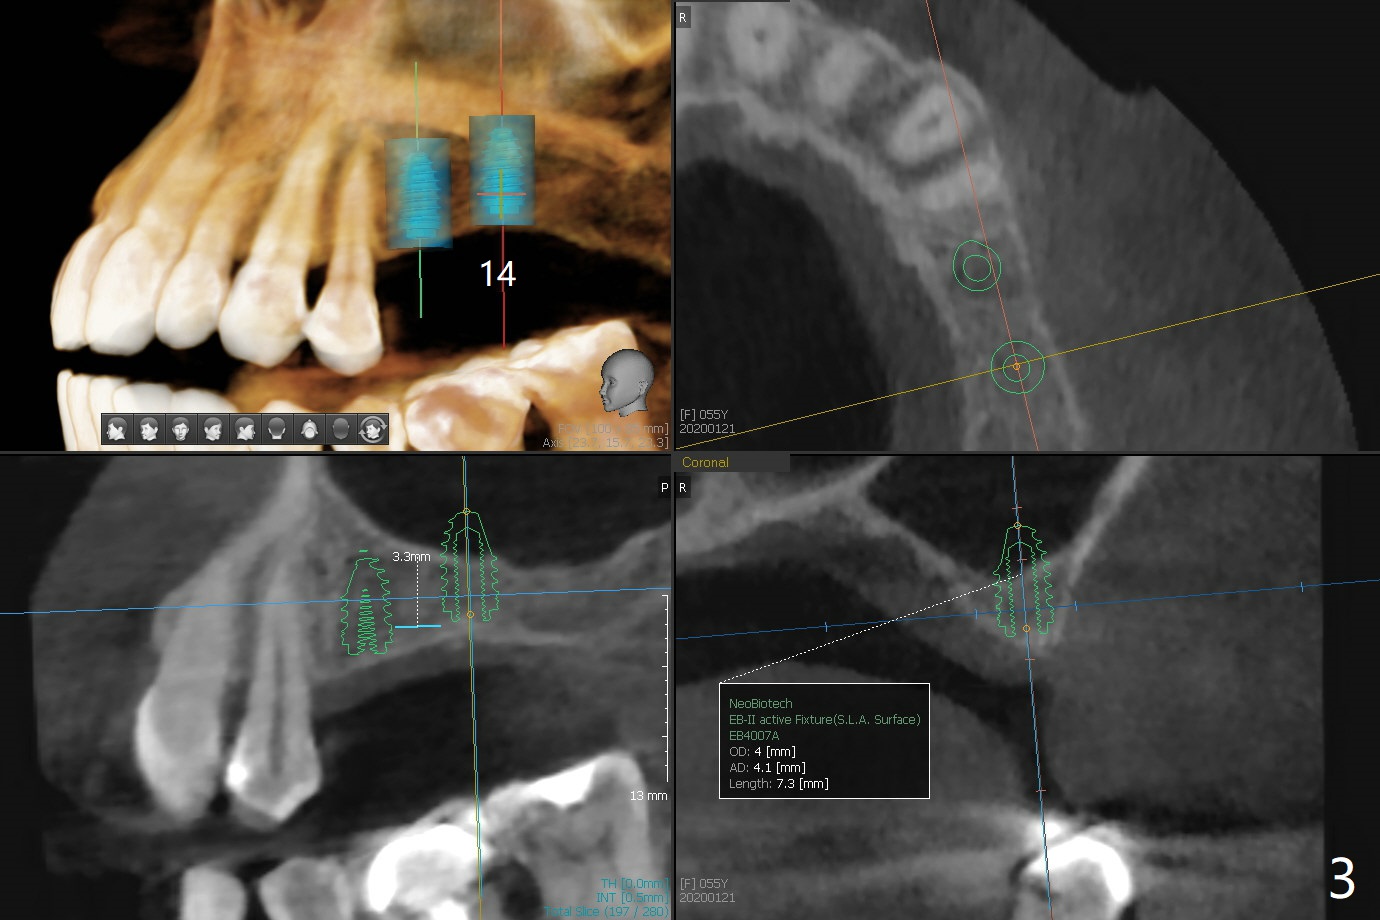

A 55-year-old woman agrees to have implants at #13 and 14 (Fig.1). There is no vertical space for implant at #15 because of supraeruption of #18 (^). A short FC implant will be placed at #13 without sinus lift (Fig.2), while sinus lift is required at #14 (Fig.3) using sinus lift drill or Magic sinus lifter. Prepare PRFx2 and small amount of sticky bone to cover #14 implant. Use acrylic to cover the bone graft. The acrylic will be retained by #13 abutment.